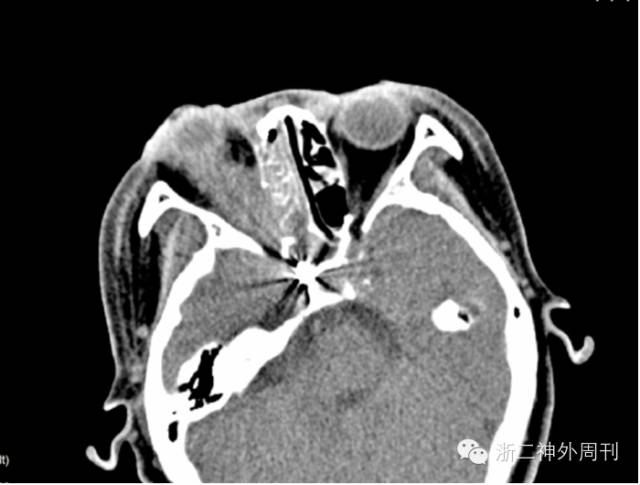

患者,女,60岁。因“外伤致眶内异物刺入,右眼失明1天”辗转多家医院后来我院。查体:意识清,无偏瘫失语及活动性鼻腔出血,右侧下眼睑见竹竿状异物刺入,少量残端外露(图1)。右瞳孔散大,无光感,眼球固定,右侧面颊部感觉障碍,左侧正常。头颅CT及CTA示(图2):右眼眶内低密度异物沿眶壁下缘刺入,长约71mm,触及右颈内动脉。

图1. 右侧下眼睑见竹竿状异物刺入,少量残端外露。

图2. CT、CTA见异物长71mm,触及右颈内动脉。